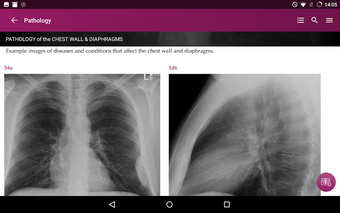

Radioloji'yi Keşfet: Göğüs Röntgeni Yorumlama, göğüs röntgeninin yorumlanmasının anlaşılmasını artırmak için tasarlanmış bir eğitim uygulamasıdır ve doktorlar, tıp öğrencileri ve radyologlar tarafından kullanılması amaçlanmaktadır. Uygulama, en küçük detayları görüntülemek için yakınlaştırılabilecek yüksek kaliteli görüntüler ve her bulgunun önemini anlamanıza yardımcı olacak bir sesli yorum içerir.

Uygulamanın amacı, kullanıcıların farklı x-ışını bulgularını ve bunların bir hastalığın teşhisinde nasıl kullanılabileceğini daha iyi anlamalarına yardımcı olmaktır. Uygulama, göğüs röntgeni yorumlaması için gerekli çeşitli yapı taşlarını kapsayan 5 bölüme ayrılmıştır.

Ayrıca, uygulama bir hastanın göğüs röntgenini incelemeleri sırasında başvurabilecekleri bir dizi nasıl yapılır içerir. Uygulamadaki nasıl yapılır adımlarını takip ederek, kullanıcılar birçok farklı bulguyu doğru bir şekilde tanımlayabilecekler ve her birini bir hastalığın teşhisi için nasıl doğru bir şekilde kullanacaklarını öğrenebileceklerdir.